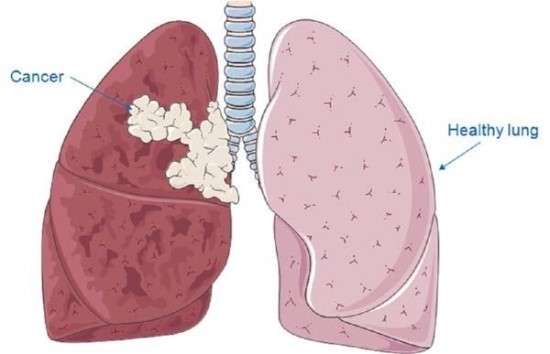

폐암은 암세포가 커지거나 주변 기관으로 전이되면서 다양한 증상을 유발합니다. 증상이 나타났을 때는 이미 어느 정도 진행된 경우가 많으므로, 아래 증상들을 주의 깊게 살펴봐야 합니다. 다음은 폐암 환자들이 흔히 겪는 10가지 주요 초기 증상입니다.

- 호흡 곤란 및 흉통

- 설명: 폐암 세포가 커지면서 기도를 좁히거나, 흉수(가슴에 물이 참)가 발생하면 숨이 차고 호흡이 곤란해집니다. 처음에는 운동할 때만 숨이 차다가, 병이 진행될수록 가만히 있어도 숨쉬기 힘들어집니다. 또한, 암세포가 흉벽(갈비뼈, 늑막)으로 전이되면 날카롭거나 둔한 흉통이 발생할 수 있습니다.